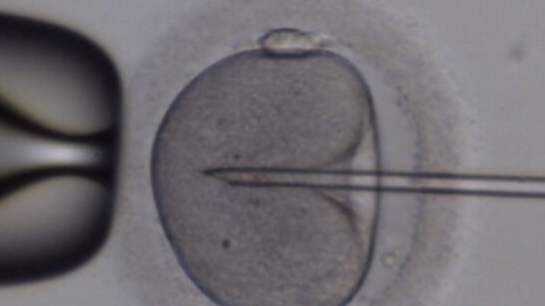

第三代试管婴儿技术,即胚胎植入前遗传学检测(PGT),通过体外受精结合胚胎遗传学筛查,帮助有遗传疾病风险或高龄不孕的夫妇实现健康生育。其核心…2026-04-28